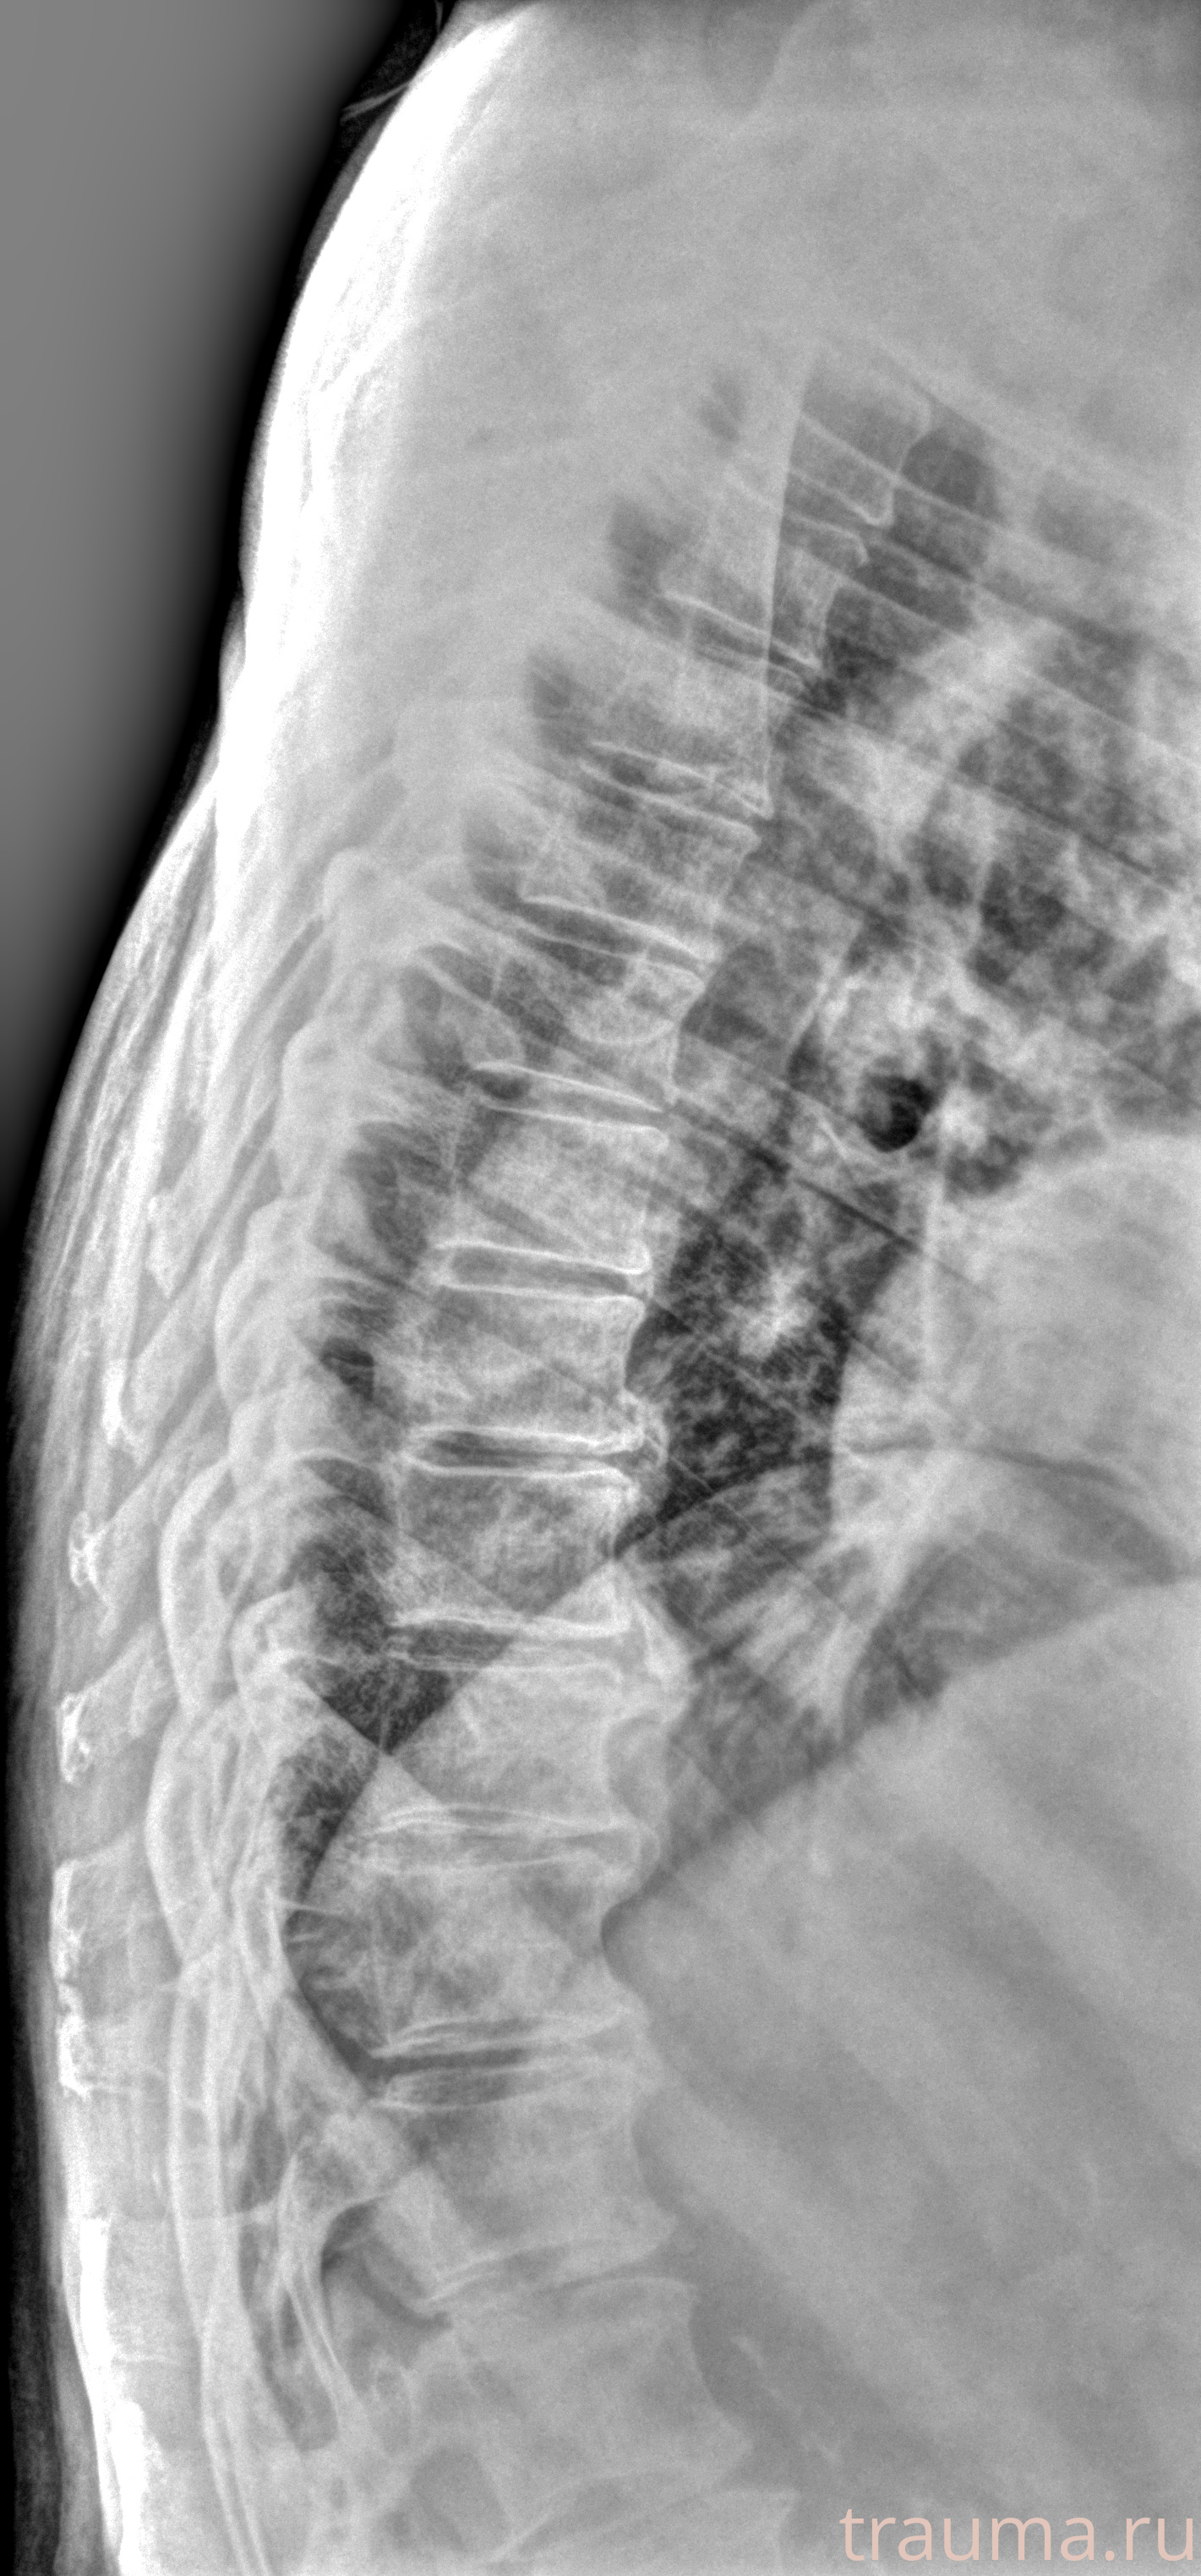

Рентген на дому: по вашему адресу приезжает врач-рентгенолог, травматолог-ортопед с мобильным рентгеновским аппаратом, проводит диагностику травмы или заболевания, делает необходимые рентгенограммы, дает рекомендации по дальнейшему лечению. Получить качественные снимки в домашних условиях возможно благодаря уникальной методике, разработанной МосРентген Центром для института  Склифосовского